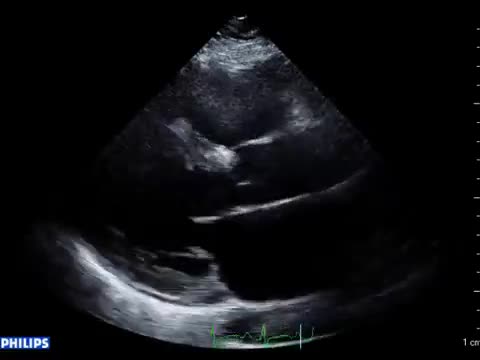

• 症例7 30代男性.拡張型心筋症

• 図2 心尖拍動 a

• 図3 傍胸骨拍動 a

• 図4 心音